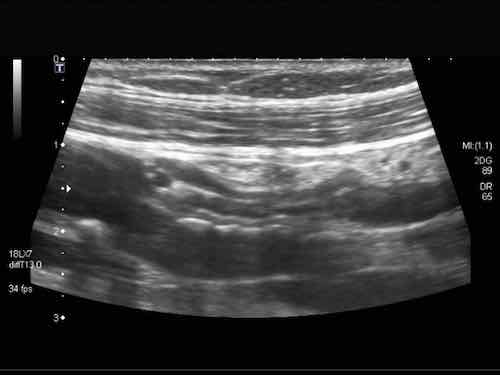

Đây là hình ảnh của hồi tràng tận cùng ở ba trẻ em và người trẻ tuổi khác nhau với các mảng Peyer lớn biểu hiện dưới dạng dày lớp niêm mạc sâu không đối xứng, giảm âm.